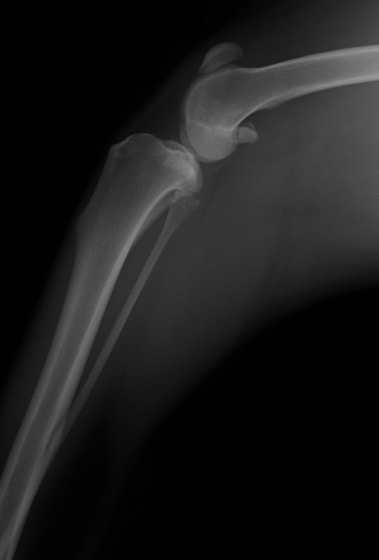

■ 症例24 キャバリア 7か月

左右膝蓋骨内方脱臼(左:グレードⅣ 右:グレードⅢ)

以前から左右後肢の跛行が認められ、整形外科学的検査・レントゲン検査により左右の膝蓋骨脱臼が認められた。症状が重度である左膝の膝蓋骨脱臼整復術を行った。外科手技は縫工筋及び内側広筋の解放、脛骨粗面の外側転位、滑車ブロック形造溝術、内外側関節方の縫縮を実施した。術後一か月時点で、左の膝蓋骨は安定しており経過は良好である。

本症例は成長期における重度の膝蓋骨脱臼であり、術後の再発の可能性もあるため、経過をしっかりと観察していく必要がある。また、今回手術を実施していない右膝に関しても経過を観察し、手術を検討していくこととする。